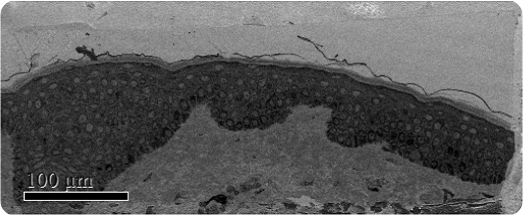

Melasma, a common dermalogical skin disease, involves the appearance of a dark skin discoloration on areas of the face upon sun exposure. The structural changes of melanocytes were studied by J.Y. Mun et al after subjecting them to Q-switched Nd:YAG laser exposure using SBFSEM (Figure 1). Melanocytes are present in the bottom epidermis layer and their dendrites can be found across all epidermis layers (Figure 2).

Figure 1. Low magnification SBFSEM image displaying the entire block-face sample with a field of view of 200 x 500μm.